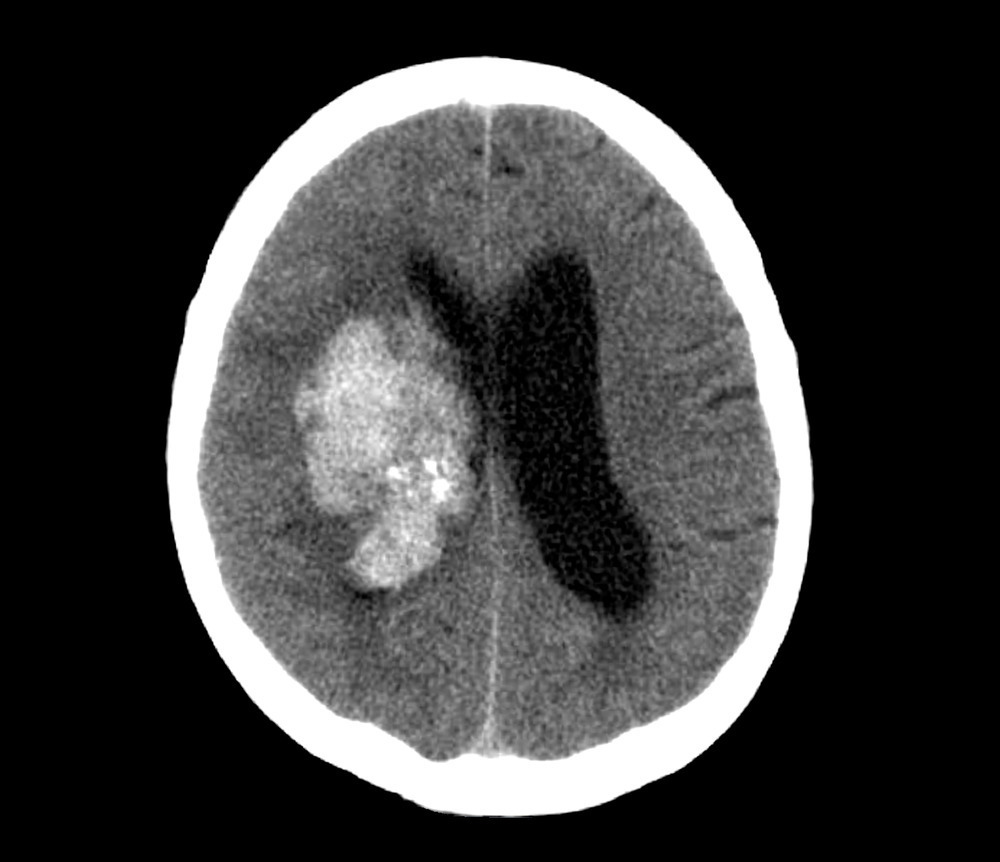

얼마 전 한 대형 병원 간호사가 근무 중 뇌출혈로 쓰러졌는데 병원에 수술할 ‘뇌혈관 외과 의사’가 없어 숨진 사실이 알려졌습니다. 이 소식이 전해지고 많은 댓글들이 달렸습니다. 그리고 그 대부분의 댓글은 ‘의사는 나쁜 놈’으로 비난의 여론이 높아졌죠.

뇌는 우리 몸의 중추 신경이 가장 많이 모여있는 곳입니다. 그래서 뇌와 뇌혈관 관련 수술은 신경외과에서 합니다. 또, 척추 신경 또한 우리 몸의 중추 신경이라 척추 관련 수술도 신경외과에서 하죠. (단, 척추 수술은 정형외과에서도 합니다) 신경외과 전공의(레지던트) 과정에서는 이 두 가지를 모두 배우기 때문에 신경외과 전문의는 이 두 분야 모두 전문적인 지식을 가진 것은 맞습니다. 하지만, 전문의가 된 후 뇌를 더 깊게 전공하려는 사람보다 척추를 전공하려는 사람이 훨씬 많습니다. 이는 뇌 분야의 일할 자리가 압도적으로 부족하고, 그에 비해 일은 엄청나게 힘들기 때문이죠. 그래서 그날 뇌혈과 의사가 병원에 없었다기 보다 뇌혈관 의사가 전체적으로 부족하다는 것이 본질입니다. 일할 자리가 부족해 지원이 적고, 지원이 적다 보니 또 일할 자리가 부족하고...악순환의 고리와도 같죠.